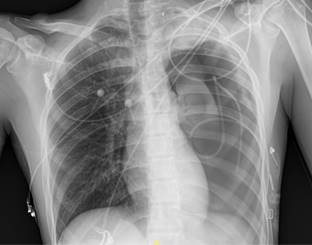

En tomografía axial vascular se evidencia sangrado activo, con probable dependencia de primera arteria intercostal izquierda. Mediante radiología intervencionista se realiza embolización con coil de 3 mm, aspirando 350 mL de líquido hemático, y posteriormente desaparece el derrame. Se envía a UCI para monitorización. A las 48 h, presenta empeoramiento clínico y radiológico, ya que aumentó el neumotórax al 65%, se detecta colapso pulmonar ipsilateral (Figura 3) y derrame pleural. Se decide realizar aspiración con jeringa a través de Pleurocath® obteniendo 70 mL drenaje hemático con componente aéreo. Se deja aspiración a 30 cmH2O, la cual se retiró tras la reexpansión pulmonar. Cabe señalar que permaneció hemodinámicamente estable en todo momento, sin necesidad de soporte hemodinámico ni transfusional. El paciente se egresó sin más eventualidades.